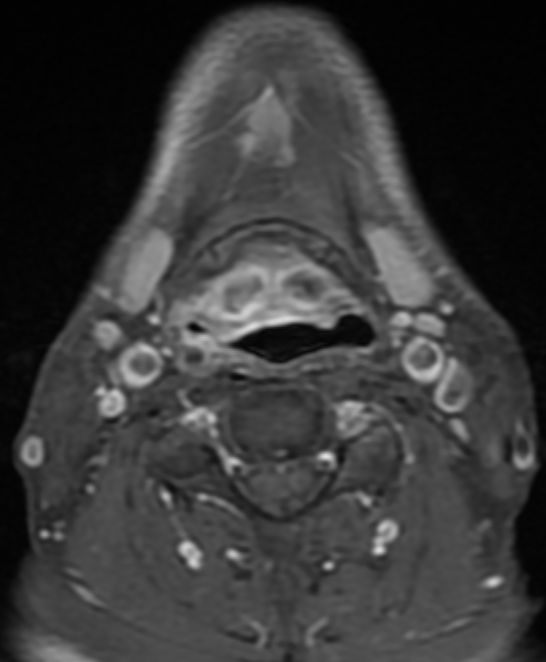

MRT: supraglottisch T3 No |

57-jähriger Mann mit langjährigem Alkohol- und Nikotinabusus. Seit 6 Monaten Schluckbeschwerden. Jetzt zunehmende Kachexie. MRT: Ausgedehntes supraglottisches Larynxkarzinom mit Schildkrorpel-Infiltration. Kehlkopfteilresektion mit ND. Histologie: unverhornendes Plattenepithelkarzinom, V0 R1 G1 - 2 Stadium post OP: pT3 pN0 (0/7) M0 | ||